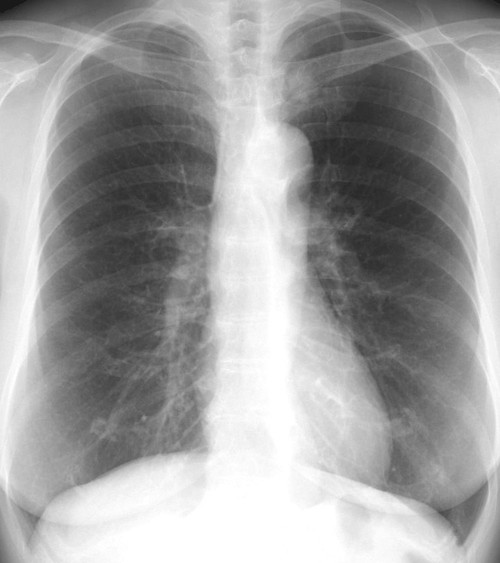

何処に異常陰影があるでしょうか?

肩甲骨に重なって見逃しやすいが、仮骨形成が始まった右第7肋骨骨折を診断できる。

右第4肋骨と胸椎の肋骨頭関節に関節面に一致して陰影をみとめる。

左鎖骨、胸鎖関節に近接した約1.5cmの円形陰影があり、辺縁は不規則(毛羽立ってみえる)になっている。陰影は大動脈・縦隔とのシルエットサインはみられず左肺S1+2に存在すると考えられ、肺門部のリンパ節腫脹はみられない。

縦隔陰影の拡大、大動脈の拡張をみとめる。右肺門肺動脈に重なって半球様の陰影(径2.7cm)が確認できる。肺門のリンパ節腫大等はない。

[評価]S6の炎症性偽腫瘍、結核、肺がん等の可能性がありCT等の検索・喀痰細胞診・生検が必要になる。